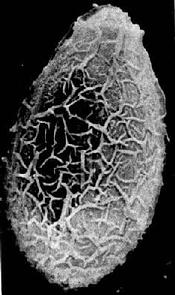

華支睪吸蟲蟲卵華支睪吸蟲蟲卵通過第一中間宿主(淡水螺螄)和第二中間宿主(淡水魚蝦)後發育成囊蚴,活的囊蚴被攝入後,經膽汁激活,囊內幼蟲破囊壁而出,經膽總管進入肝膽管發育為成蟲,亦可通過血管或穿過腸壁到達肝臟,最後寄生在肝膽管內發育為成蟲,成蟲的壽命一般為20-30年,主要寄生在人、犬、貓和豬的肝膽管內,蟲數多時亦可移居較大的膽管甚至膽囊內,偶爾在胰管內亦可發現成蟲。

華支睪吸蟲蟲卵1.蟲卵檢查 糞便中找到蟲卵可以確診華支睪吸蟲病,檢出率約50%左右。常用的方法有直接塗片法、水洗沉澱法、改良加藤厚膜塗片法及醛醚法後2種方法檢出率較高。直接從十二指腸引流液中檢查蟲卵,檢出率接近100%因操作麻煩,增加病人的痛苦,不宜常規使用。